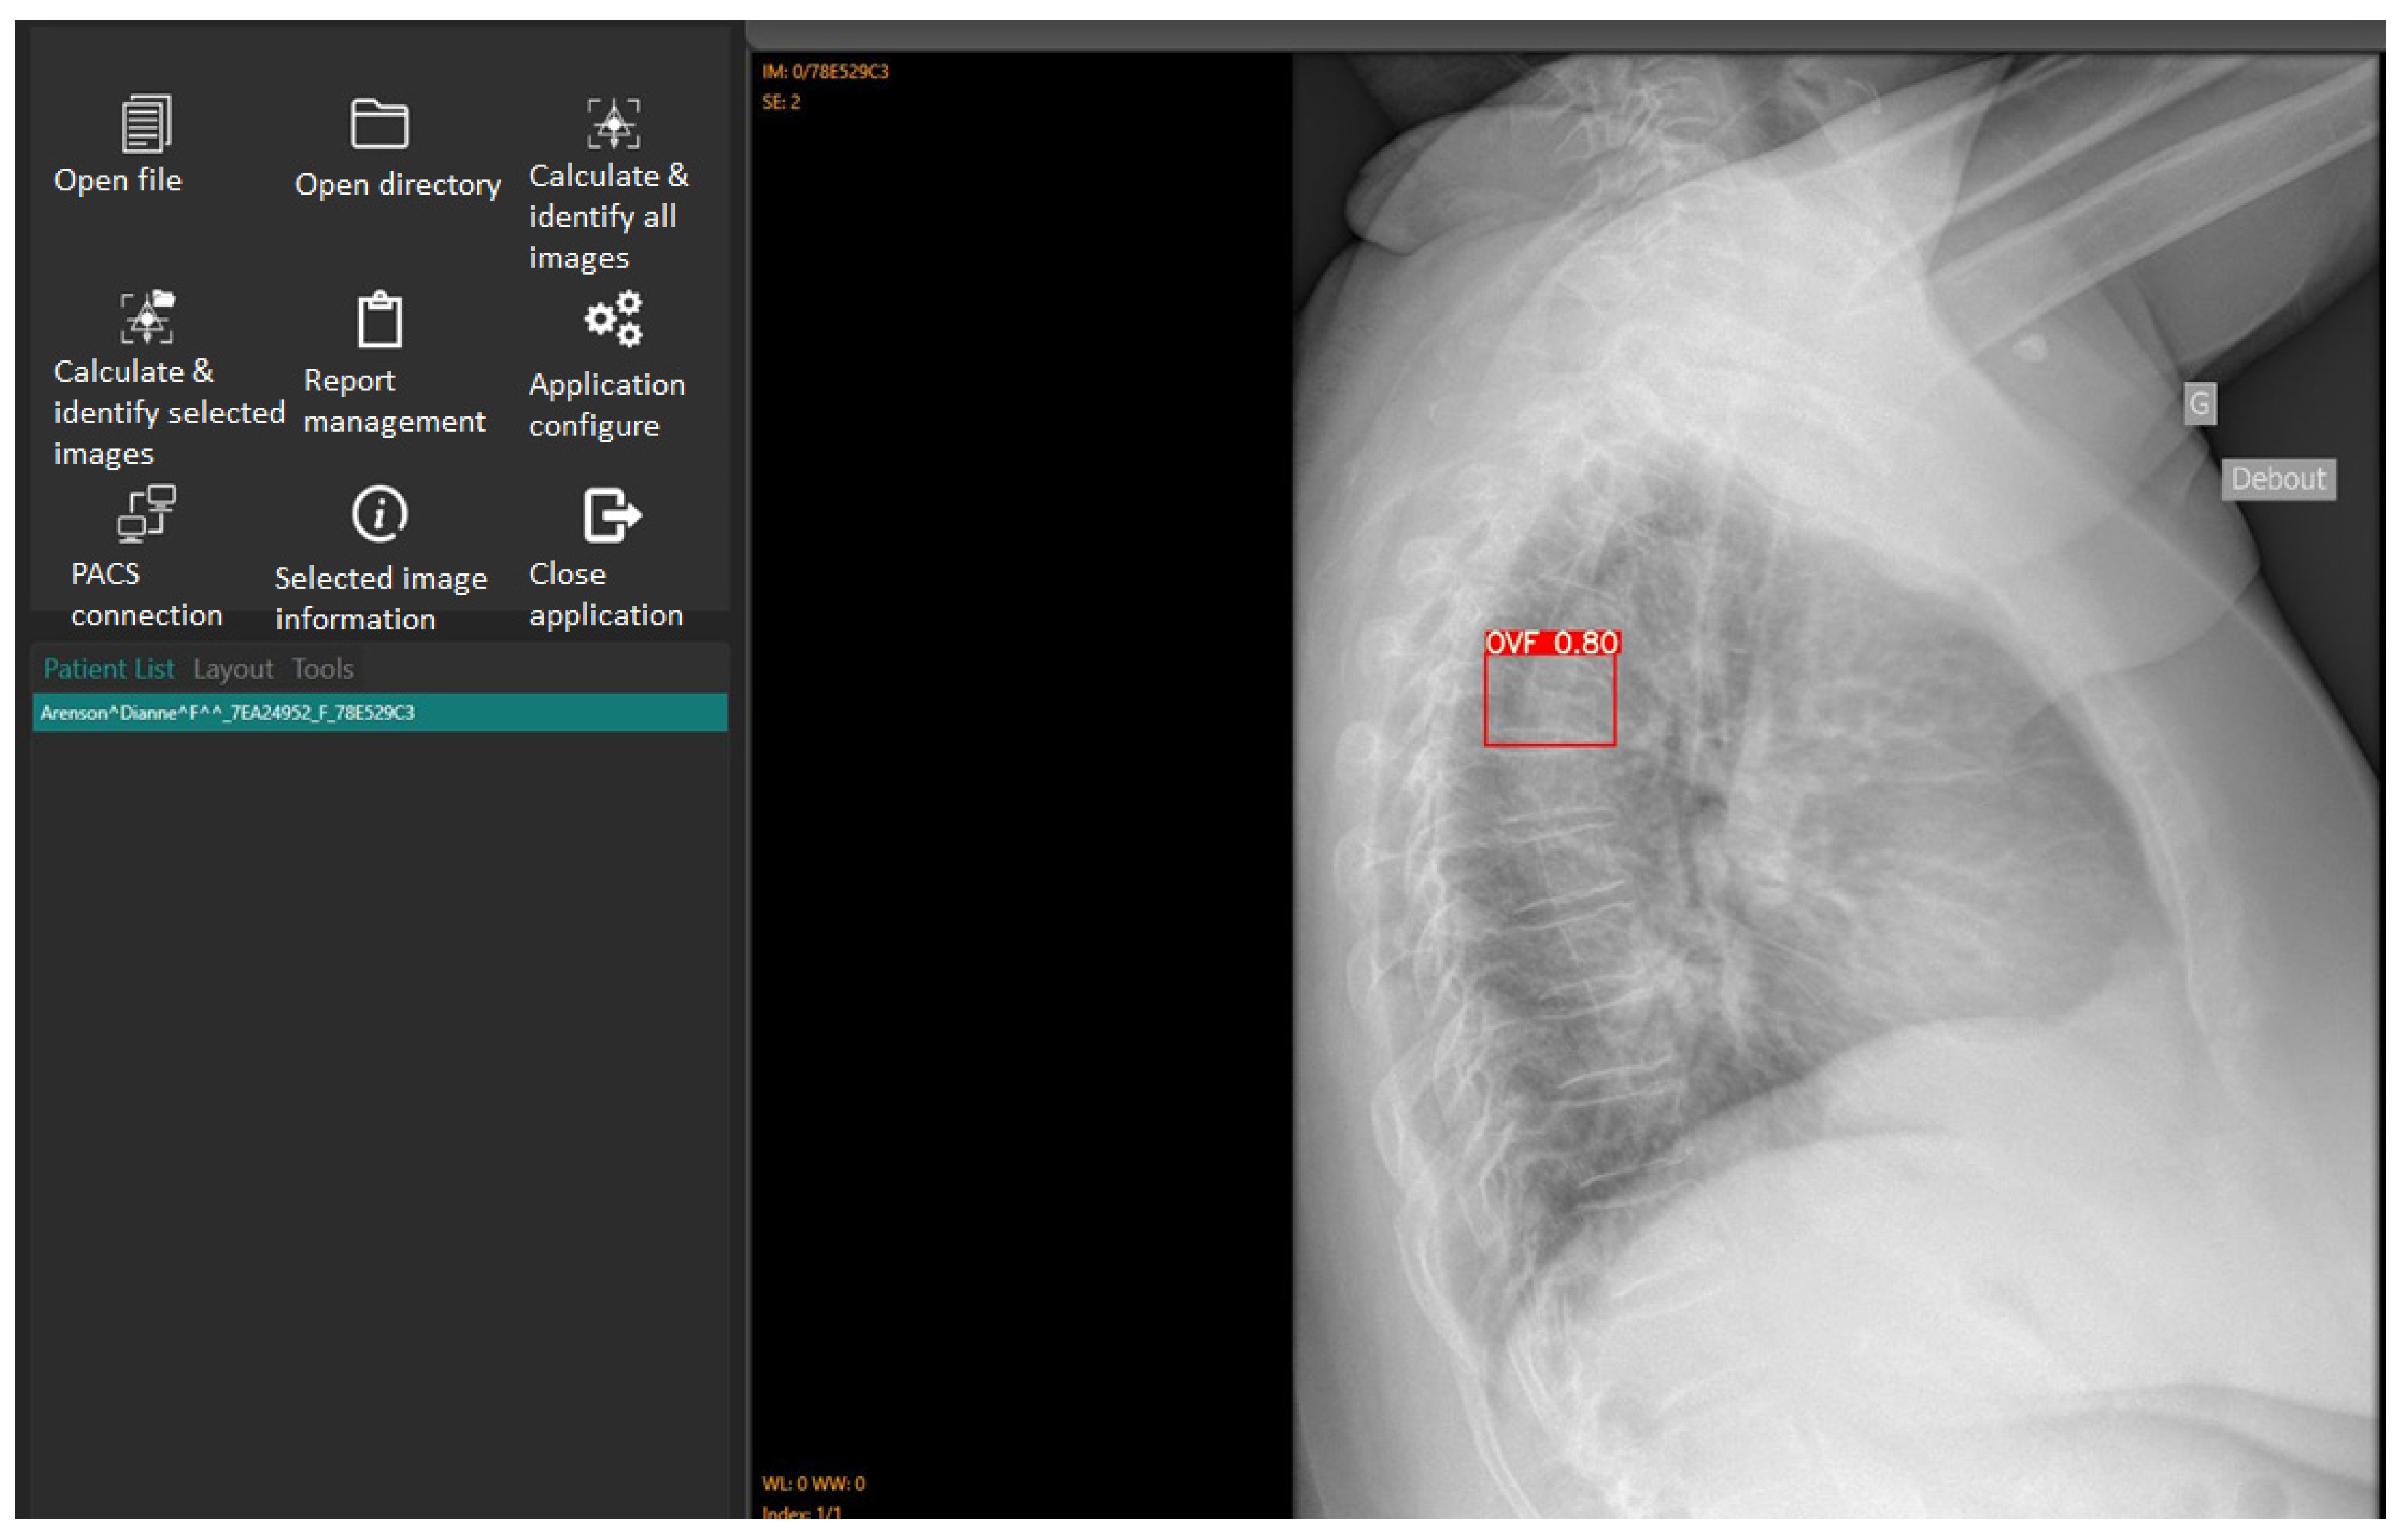

2.2. Image Analysis Using Ofeye 1.0 for Automatic Detection of OVFs

- Xiao, B.H.; Zhu, M.S.; Du, E.Z.; Liu, W.H.; Ma, J.B.; Huang, H.; Gong, J.S.; Diacinti, D.; Zhang, K.; Gao, B.; et al. A software program for automated compressive vertebral fracture detection on elderly women’s lateral chest radiograph: Ofeye 1.0. Quant. Imaging Med. Surg. 2022, 12, 4259–4271. [Google Scholar] [CrossRef]